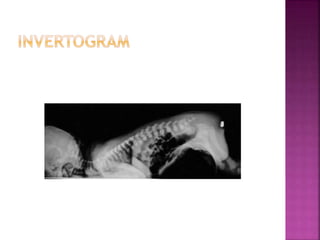

• High variety of malformation 

If the rectum is blind ending above the

levator funnel.

• Low variety of malformation 

If the rectum passes through the anorectal

pouch opens out on the skin either at the site of the

anus or anteriorly on the perineal or scrotal raphe

in the male or in the vestibule or vulva in the

female.

• Intermediate variety  Fistula to the posterior

urethra in the male , or vestibule in a female.

• High varietyof malformation  If the rectum is blind ending above the levator funnel. • Low variety of malformation  If the rectum passes through the anorectal pouch opens out on the skin either at the site of the anus or anteriorly on the perineal or scrotal raphe in the male or in the vestibule or vulva in the female. • Intermediate variety  Fistula to the posterior urethra in the male , or vestibule in a female.